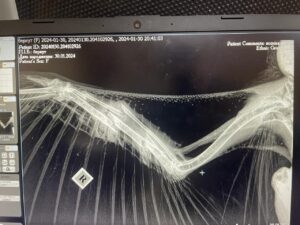

Ukrainan BirdLifen avulla Klasu löytyi kuolleena 15.12. Lintu otettiin tarkemmin tutkittavaksi, ja röntgenkuva paljasti kuolinsyyksi salametsästäjän aseesta peräisin olevan haulin. Laiton tappaminen on tärkeimpiä petolintujamme uhkaavia tekijöitä niiden muuttomatkan varrella ja talvehtimisalueilla.